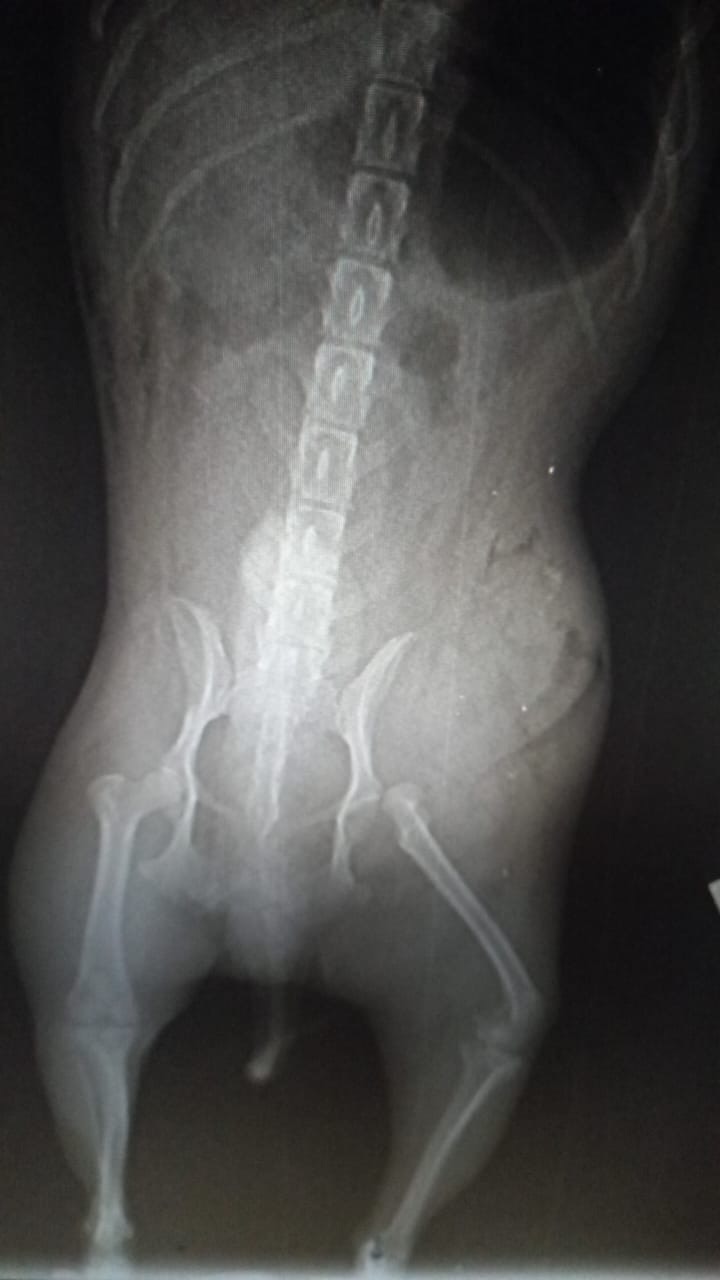

Il est borgne à la suite d’une blessure à l’œil droit non soigné. Il a un souffle au cœur qui sera mieux détaillé à son arrivée en France et son traitement sera adapté. Il a malheureusement été attaqué par un gros chien sans laisse et a été gravement blessé : il a subit 2 chirurgies pour soigner la luxation de la hanche et la hernie abdominale.